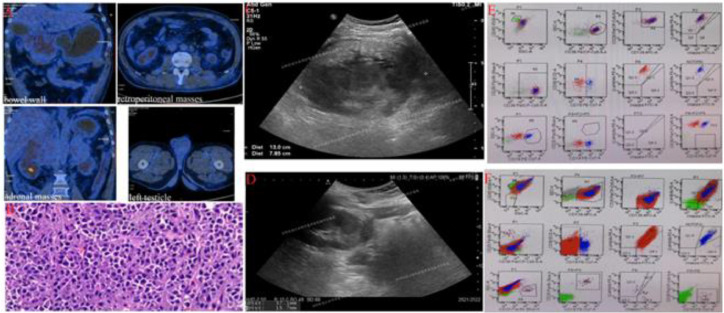

Abdominal multiple extramedullary plasmacytoma (EMP) is a rare disease. CD38-negative relapsed/refractory EMP after treatment with daratumumab has never been reported. In 2020, a patient with jaundice was diagnosed with plasmacytoma in another hospital, which progressed one year after receiving multiline therapy. In July 2021, he was admitted to our hospital and showed CD38-pogative plasmacytoma. The patient received 2 cycles of treatment including daratumumab, venetoclax and DCEP chemotherapy and achieved partial remission. However, he developed ascites and eventually died. Our case indicated that multiple EMP has much lower incidence and far worse prognosis than solitary EMP.